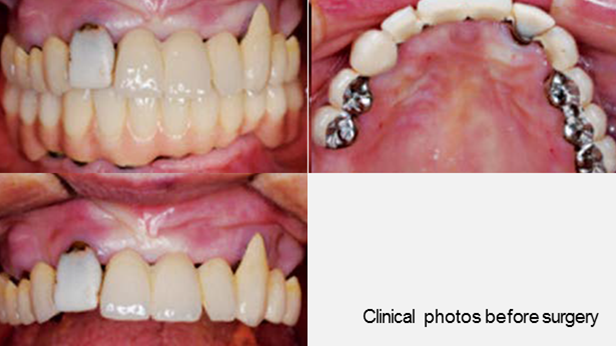

Clinical case: AFull transition from natural teeth to all-on-6 bridges

with AnyRidge implants

- Courtesy of Dr. Rabih Abi Nader, UAE -

Keywords

Full-mouth rehabilitation, minimal layering, Zirconia, all-on-6, life changing result, edentulous ,Dr. Rabih Abi Nader, AnyRidge

Products:

AnyRidge implant system